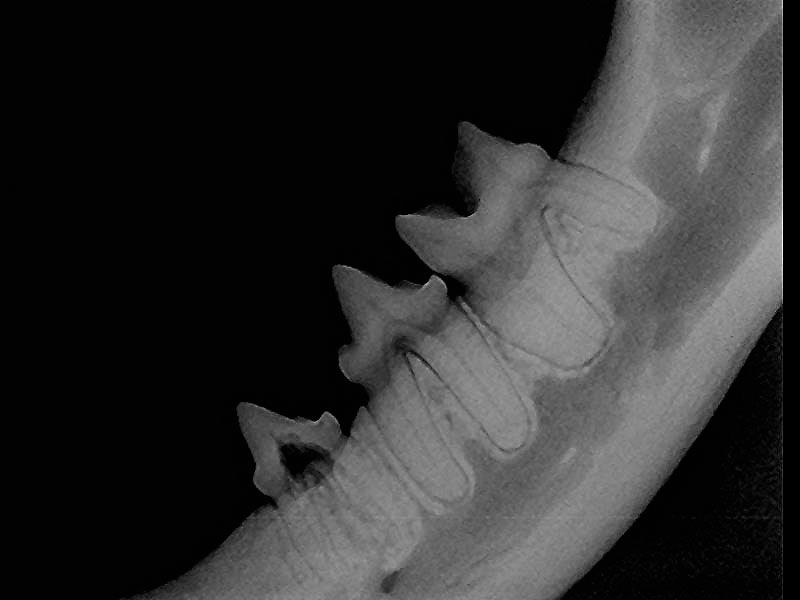

Tooth Resorption In Dogs And Cats Vetbloom Blog

Tooth Resorption Upstate Vet